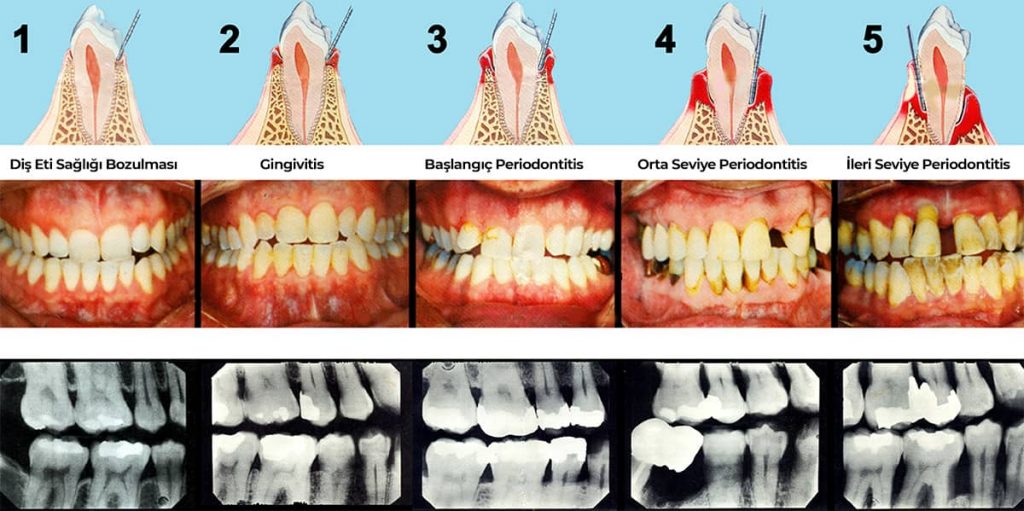

Diş eti hastalıkları, diş eti iltihabı (gingivitis) ile başlar. Aslında gingivitis diş eti hastalığının erken dönemidir denilebilir. Gingivitis döneminde diş etleri, kanamalı, kırmızı ve hacimce genişlemiş yapıdadır. Diş eti hastalıkları erken dönemlerinde kişiye çok fazla rahatsızlık vermeyebilir. Tedavi edilmediği sürece sıradan bir diş eti hastalığı olan gingivitis periodontitise ilerleyerek diş eti ve dişleri destekleyen kemik yapıda da geriye dönüşü olmayan hasarlar bırakabilir.

Periodontitis

Periodontitis, diş eti hastalıkları arasında en ilerlemiş olanıdır. Dişleri destekleyen diş eti dokusunun yanında alveol kemiğinde de hasara yol açar. Diş ve diş eti arasında "periodontal cep" denilen bir cep oluşur ve bu cebin içinde diş taşı ve plak gibi birçok ağız hijyenini bozabilecek şey oluşur. Bu bakteriyel oluşumların diş taşı temizliği ile temizlenmesi gerekir. Ceplerin temizlenmediği durumlardaysa enfeksiyonun yerleşmesi ve hastalığının daha fazla ilerlemesini kolaylaştırıcı bir rol alır. Bu hastalık ilerledikçe dişler sallanmaya hatta düşmeye başlayabilir.